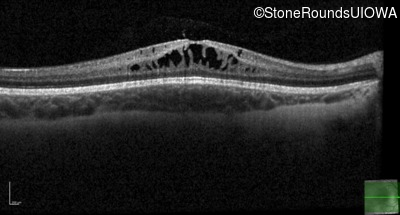

This 6 year old boy first experienced difficulty reading and seeing the blackboard at age 5.

| Age at visit: 6 years |

| Age at visit: 11 years |

| Age at visit: 14 years |

| Age at visit: 14 years (Visit 2) |